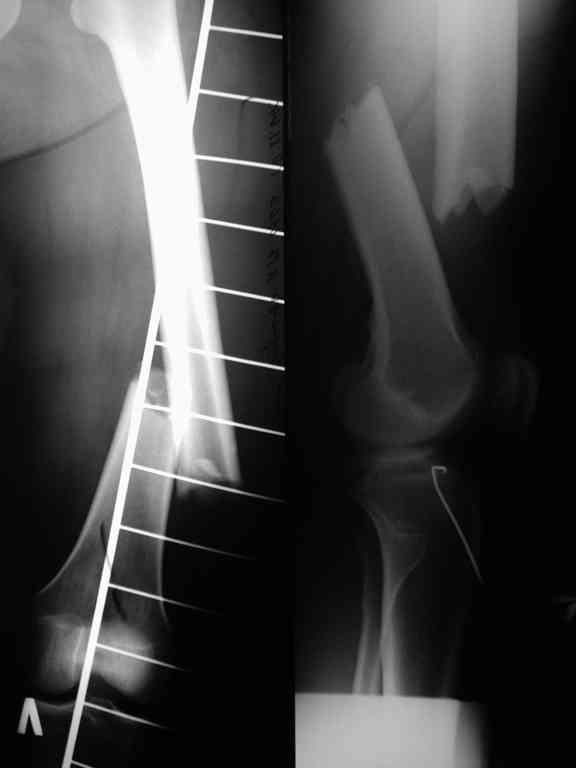

В приложении рентгенограмма бедра за авгутст 2005 с согнутым гвоздем и первичные.

Отсутствие сращения косвенно говорит об этом. Хотя, судя по снимкам со стержнем, вероятны и другие проблемы. Раз есть диастаз - надо динамизировать стержень практически сразу, недели в 2-4 после остеосинтеза, а раз уж сращения в динамике не выявляется, зачем было с динамизацией ждать больше 2 мес.?

Мы перестали последние годы применять столь тонкие бедренные гвозди, т.е. встречаемость проблем с ними выше. 10 мм минимум, только в основном у молодежи, остальным потолще. "Рассверливали долговато" - что за трудности подразумеваются?

Обычно достаточно закрыто перештифтовать стержнем большего диаметра, рассверлив канал. Зачем перешли на пластину?

> Вариант интрамедуллярного остеоснтеза мы рассматриваем. Обсуждается

Вариант с аппаратом вполне рабочий, даже пластину можно не удалять, но - все известные минусы аппаратного лечения, плюс иной раз рефрактуры после снятия. Так что IMHO думать тут особо не о чем. Раз нет инфекции, то мы бы малоинвазивно убрали пластину и винты, да и заштифтовали бы с рассверливанием, динамически сразу. Раз уже делали через колено - то новй канал тогда и не делать.